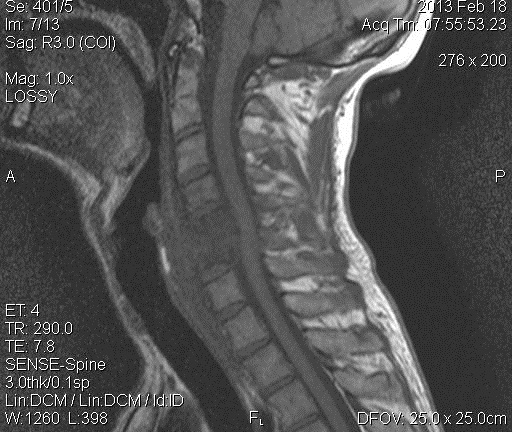

Магнитно-резонансная томография

Диагностика заболеваний поясничного отдела позвоночника часто включает магнитно-резонансную томографию. Этот метод более безопасен и точен. На МРТ костные ткани отображаются черным цветом, а мягкие — в различных оттенках серого. Это позволяет выявлять даже небольшие опухоли, кисты и инфильтраты. Лечение антибиотиками при спондилодисците начинается только после определения типа инфекционного агента, для чего проводятся анализы крови. Увеличение числа лейкоцитов и скорость оседания эритроцитов (СОЭ) указывают на наличие воспалительного процесса. Реакция Пирке используется для выявления туберкулезных форм заболевания.